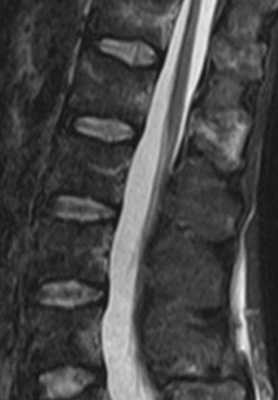

(Слева) Сагиттальный срез, Т1-ВИ, 70-летняя женщина с длительным анамнезом тромбоцито-за и развившейся в последующем панцитопении: распространенное несколько неоднородное снижение интенсивности сигнала костного мозга. Биопсия подтвердила диагноз миелофиброза.

(Справа) На сагиттальном Т2-ВИ этой же пациентки сигнал костного мозга тел позвонков отличается низкой интенсивностью. Заболевание у данной пациентки характеризовалось рефрактерностью к проводимому лечению, однако несмотря на это она с момента постановки диагноза миелофиброза прожила 8 лет.